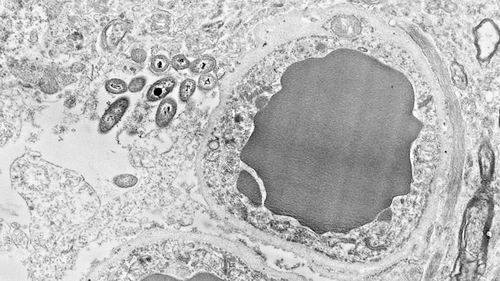

不同的拟杆菌种类(着色图中显示了五种)居住在人类肠道中,它能释放出毒素,其他细菌必须能够消除毒素的影响才能存活。图片来源:Kevin Cutler/Mougous Lab/UW/HHMI